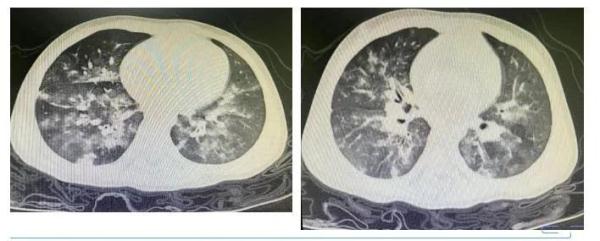

相对多数的感染者,特别是年纪较大些的儿童以及成人,其症状是比较轻微的,一般在一至两周时间内会自行趋向好转。然而对于年龄处在两岁之下的婴幼儿而言,病毒更易于朝着下呼吸道进行侵袭,进而引发毛细支气管炎或者肺炎,在这个时候就会出现较为明显的咳嗽以及喘息症状。

高热不一定会被呼吸道合胞病毒感染所引致,于成人而言,其表现或许仅仅只是感冒。该病毒的危险性大多聚焦于婴幼儿,易于引发带有喘息症状的毛细支气管炎。当下,医院用以明确究竟是何种病毒感染的诊断方式主要是抗原检测或者核酸检测。